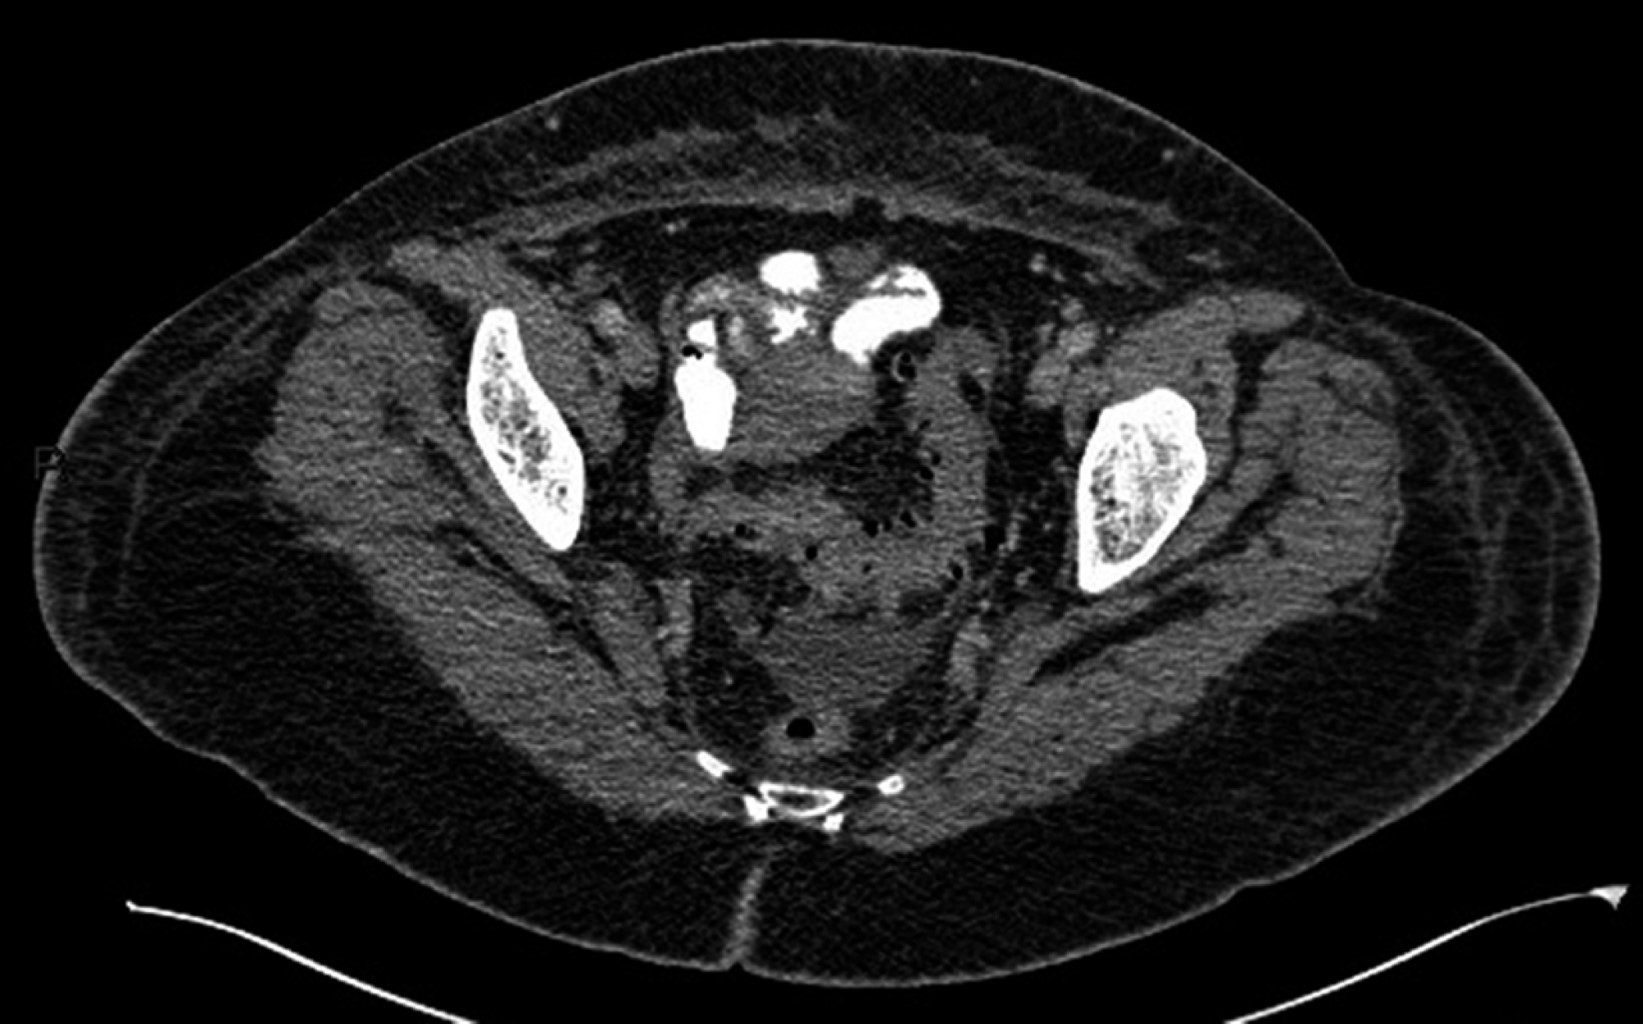

Introduction: pylephlebitis, also known as ascending septic thrombophlebitis, is characterized by embolic occlusion of the portal-venous system and its branches, secondary to intra-abdominal infection. Clinical case: a 63-year-old female came for abdominal pain, as well as a fever of 39.4 °C. They presented leukocytosis, increased C-reactive protein, procalcitonin, and liver function tests. A tomography was performed, observing air thrombus in the inferior mesenteric vein and thrombus in the left portal vein, with data of diverticulitis. Conclusions: pylephlebitis is a rare and severe complication; the radiologist must identify it to establish the appropriate medical treatment.

Figure 3